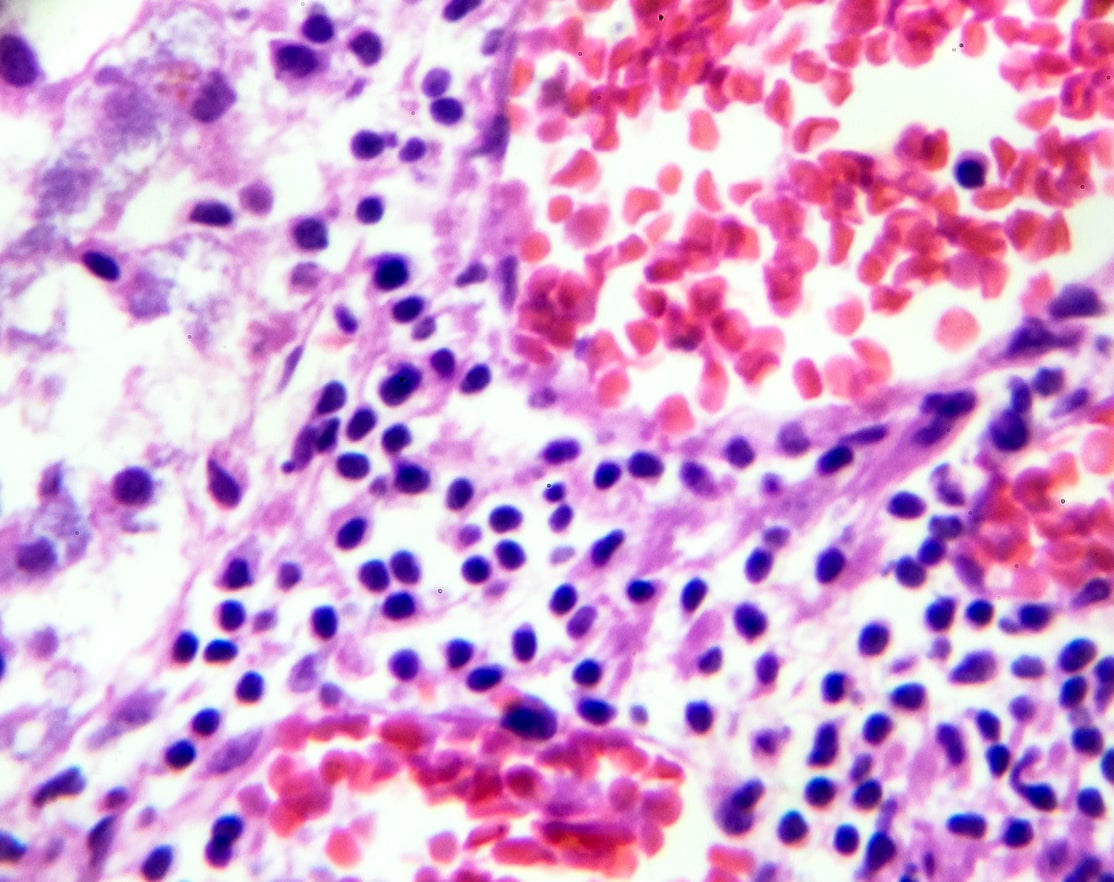

Multiple Myeloma

In multiple myeloma (MM), a cancer of plasma cells, lipid rafts are involved in tumor progression, drug resistance, and cellular communication.